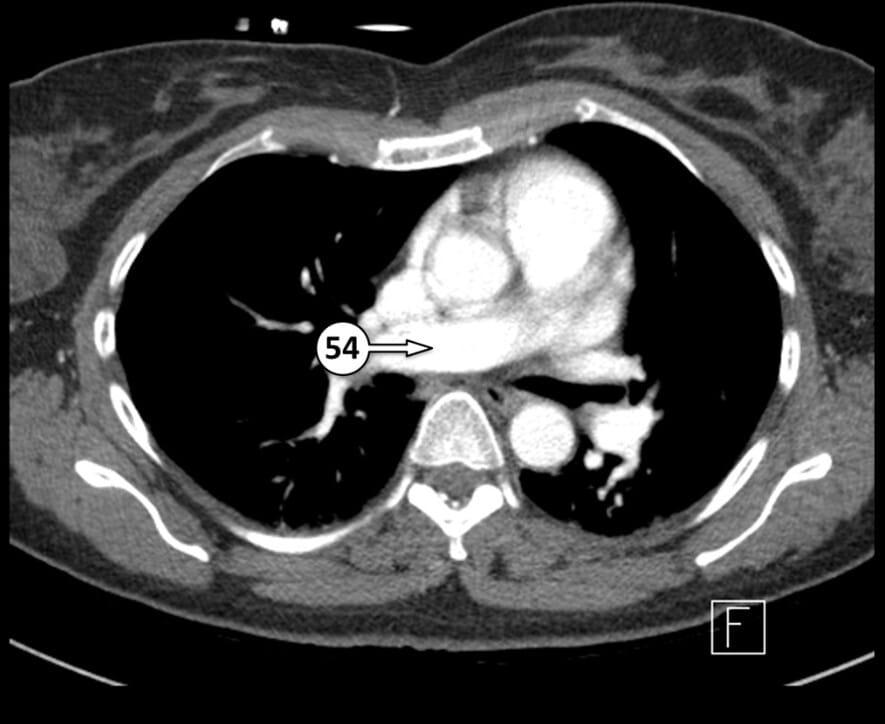

54. right pulmonary artery